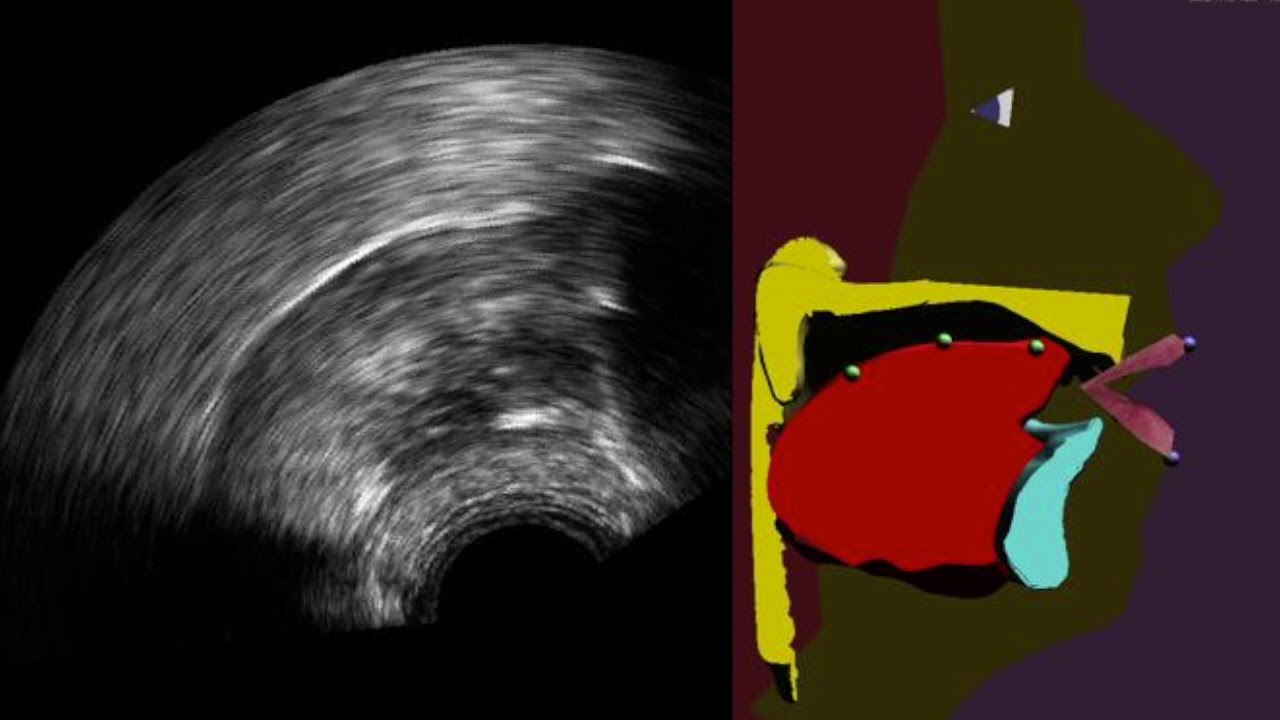

Imagen del nuevo sistema. A la izquierda, ecografía del sistema lingual, a la derecha, la reconstrucción virtual que permite observar en tiempo real los movimientos de la lengua y descubrir los defectos en la pronunciación. Imagen: CNRS

Investigadores franceses han desarrollado un sistema que permite visualizar, en tiempo real, los movimientos de nuestra lengua. Se trata de una ecografía lingual aumentada que, además de mostrar el rostro y los labios, hace aparecer la lengua, el paladar y los dientes, generalmente ocultos en el interior de la boca.

En el nuevo trabajo, los investigadores franceses mejoran este retorno visual a través de una especie de cabeza parlante articulatoria que es animada automáticamente en tiempo real a partir de imágenes ecográficas apoyadas con un algoritmo, según se explica en un comunicado.

Este clon virtual de una persona parlante permite una visualización del proceso físico de articulación de una lengua y su pronunciación mucho más intuitiva y contextualizada.